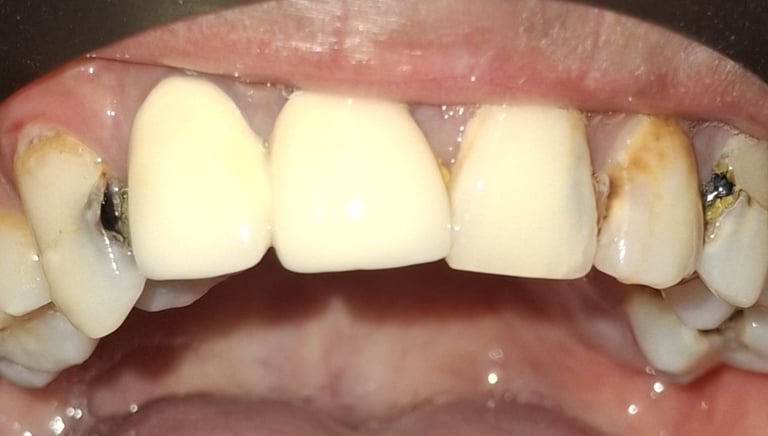

Clinical pictures of teeth requiring RCT

All images are of real cases of teeth where Root canal treatment was performed to remove infection and preserve the natural tooth restoring normal chewing and function of teeth.